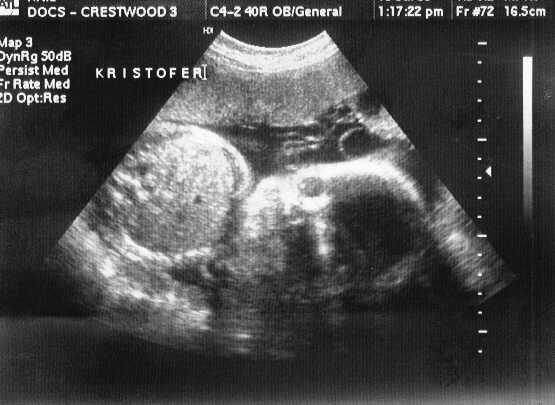

V-Twins Names

This is KRISTOFOR HENRY (or Kristofer). I was only kidding about RICO!